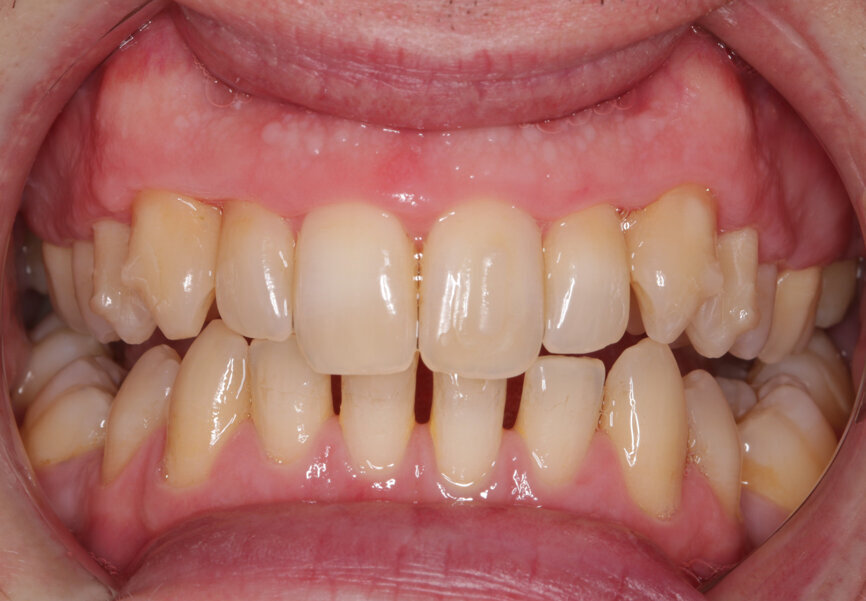

Fig. 14: Post-treatment 1

Outcome

While the patient arrived with misaligned teeth that were difficult to clean and gingivae that reflected this, he left with clean, light teeth, pink gingivae and a much straighter smile. He was very pleased and expressed warm gratitude for his treatment. He practised every bit of advice given with conspicuous diligence and as a result he reaped the rewards.

I was even happy with this having been a compromised case. Of course, a comprehensive orthodontic treatment plan would have intruded the central incisors, de-rotated the canines further and closed the mandibular spaces, but this is not what the patient wanted. His molar relationships did not change, but we affordably and conservatively made his visible teeth straighter, whiter and easier to clean, and to me this is the very essence of what GDP orthodontics is.

As the refinement aligners were progressing, I took impressions for whitening trays, and the patient wore 16% carbamide peroxide gel for three weeks between wearing his aligners. By the end, the diastema had closed and tooth #23 had improved a little but not entirely. However, the patient declared himself happy and elected for Essix retainers over a fixed wire, as he liked the idea of being able to floss all of his teeth, plus he was so used to wearing aligners that wearing retainers at night posed no problem.